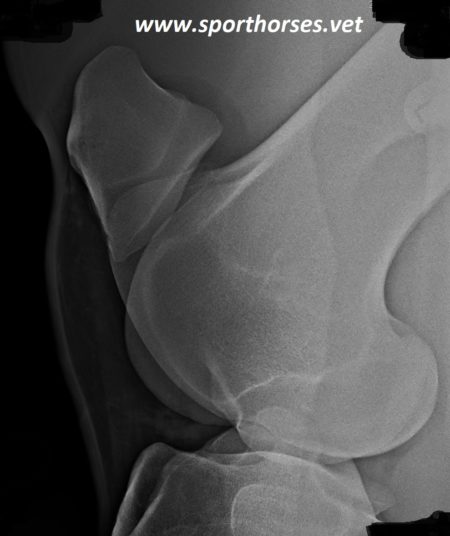

Horses have a normal “locking mechanism” associated with their stifle area that allows them to maintain limb extension without considerable muscular effort. This mechanism is called a “stay apparatus” and primarily involves the patella (knee cap), the bottom end of the femur (medial trochlear ridge), and three distal patellar ligaments (ligaments that attach to the knee cap and tibia below the stifle). Horses also have a stay apparatus in the front limb and therefore have the ability to sleep while standing. The horse’s stay apparatus is perfectly normal.

The problem arises when this locking mechanism inadvertently occurs (or “catches”) during movement. It generally results in a hypometric (toe-dragging) gait with a delayed forward phase to the stride